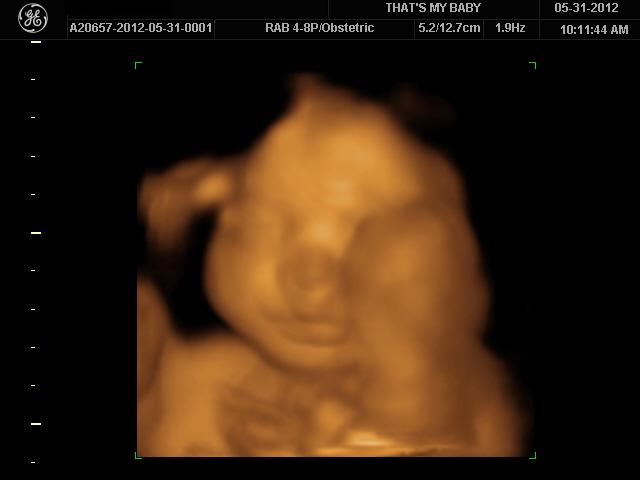

we had an elective 3D ultrasound this morning. I always thought they looked kinda alien-like, but I guess it's different when it's your own kid. Ronin, of course, was not cooperative in the slightest at first. he was sleeping like a rock and would not change positions... and when he did show his face, his put his hand up in front of it. he even put his hand in front of his face and FLICKED US OFF.

anyway, after moving around and poking him, we finally got some decent shots of his cute face. remember how my bump watch update said that he should be weighing about 2lbs? yeah, this chub weighs about 3lbs 10oz. the sonogram tech estimated that he will probably be over 8lbs at birth.

he has a large head (no surprise there... have you SEEN my husband's dome?), fat feet, and big hands. he's also got a pretty long torso, which is probably why he's weighing so much already... it also explains why I feel like he's cramped in there.

I may be biased, but I think he's pretty damn cute already! I can't wait to meet him! :D